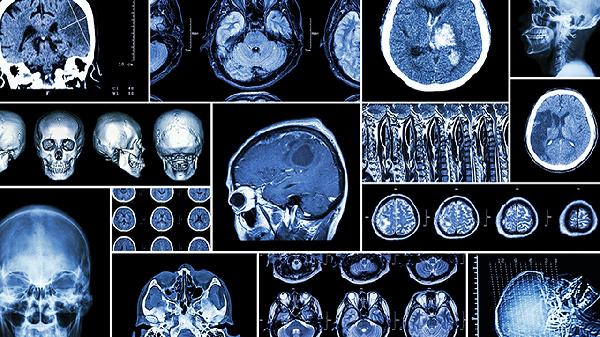

除上述禁忌外,服用脑血栓片期间应避免食用辛辣刺激性食物,戒烟限酒,保持规律作息。建议适度进行有氧运动如散步、太极拳等,但避免剧烈运动。用药期间如出现头晕、恶心、牙龈出血等异常症状应及时就诊。脑血管疾病患者需定期复查颅脑影像学和凝血功能,在医生指导下规范治疗并调整用药方案。